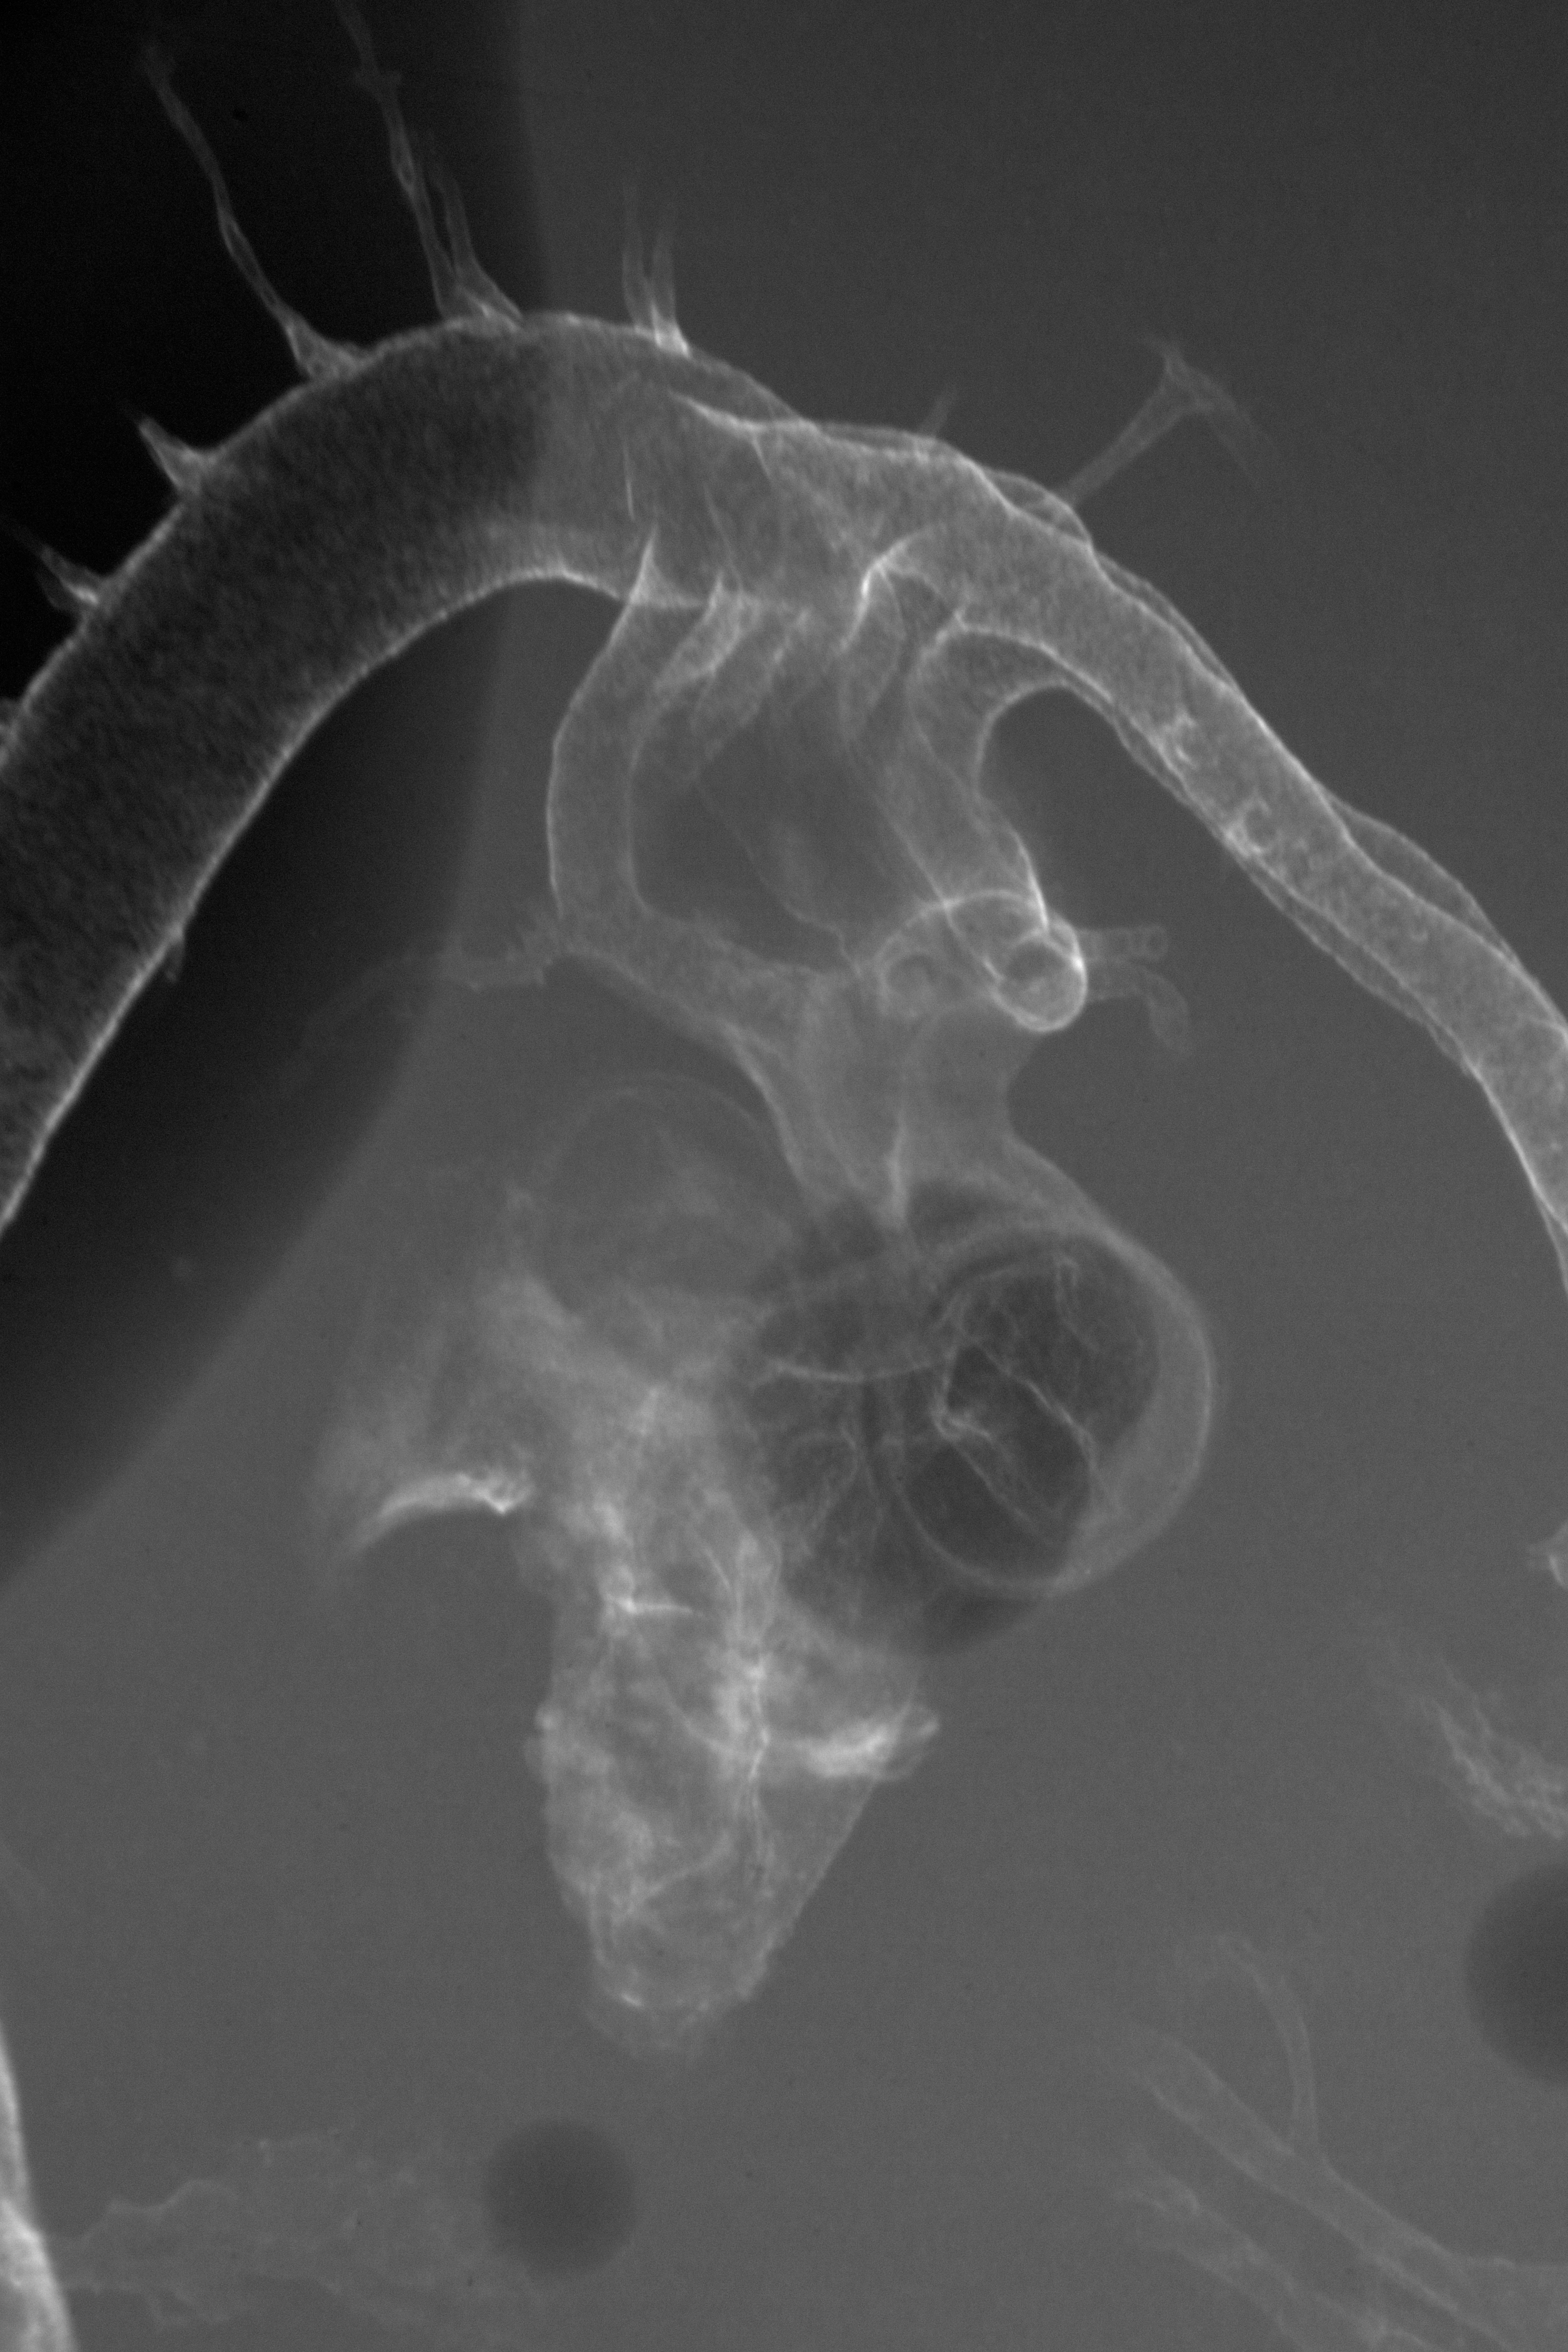

Hamburger-Hamilton (HH) Stage 23 (approx. 4 days)

X-Ray Micrographs